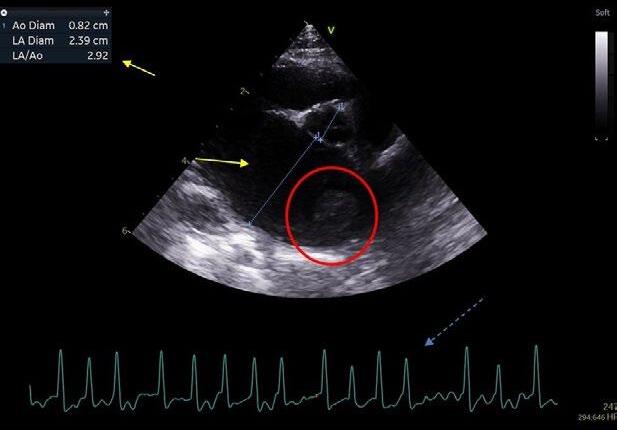

Echocardiography

Cats with HCM will typically present with left atrial and left auricular enlargement, left ventricular concentric hypertrophy and diastolic dysfunction. The presence of spontaneous echocardiographic contrast (SEC), which has a swirling smoke-like appearance on echocardiography, represents aggregation of erythrocytes in the enlarged left atria, and is indicative of stasis (reduced blood flow).9,11 In some cases, a thrombus might be seen in the left auricle or left atrium (Figure 6) The presence of increased B-lines (narrow-based ‘comet tails’ can be supportive of pulmonary oedema but is not specific to the aetiology.